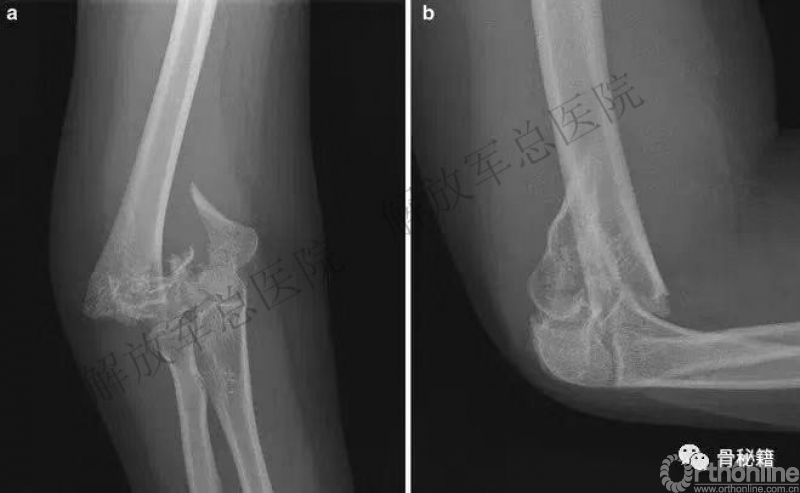

一、详细的术前评估

X线、CT、神经检查、等等。

三、充分的的骨折显露

手术入路(略)